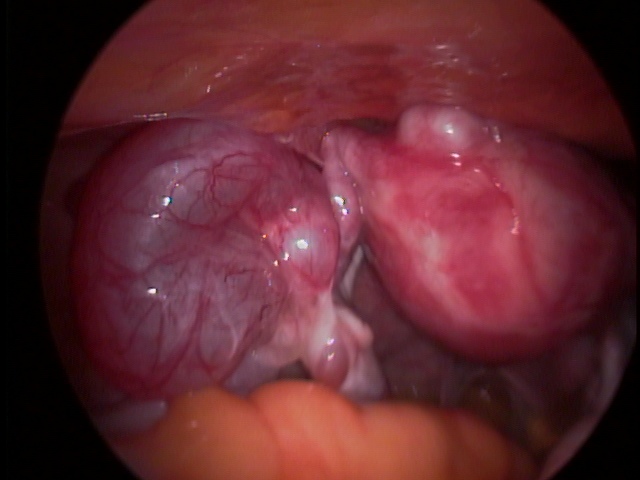

Procedimento cirúrgico que consiste na retirada de mioma intramural (localizado na parede do útero) ou subseroso (localizado fora do útero). Mioma submucoso (localizado dentro do útero) de grande volume também pode ser retirado através de laparoscopia evitando assim, um segundo tempo cirúrgico, como pode ocorrer na via histeroscópica.